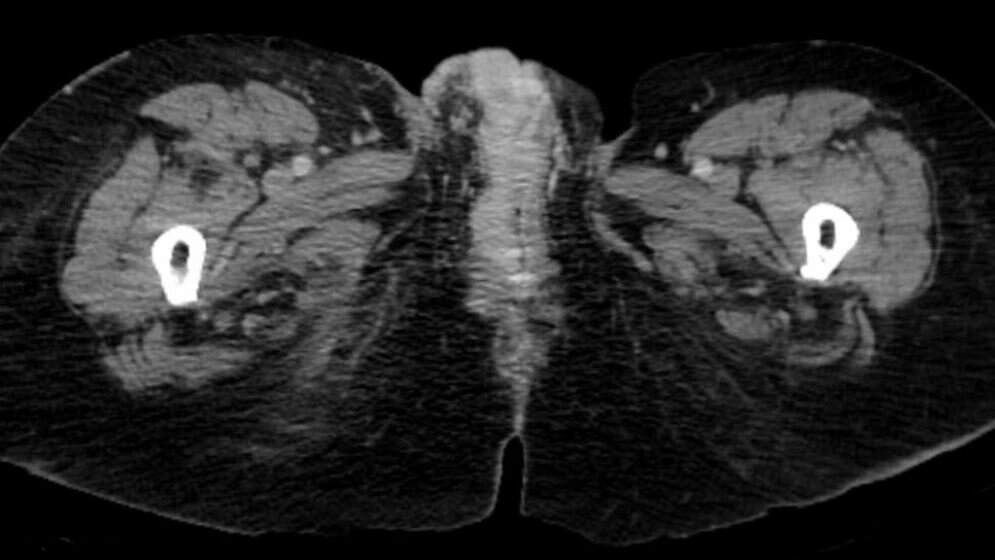

Die sichere Diagnose kann laut Prof. Dr. Hampl nur durch eine feingewebliche Untersuchung gestellt werden: „Bei allen verdächtigen Läsionen sollte deshalb eine Biopsie durchgeführt werden“, fordert sie: „Die überarbeitete Leitlinie stellt hier klare Anforderungen an die pathologisch-histologische Aufarbeitung und Befundung.“ Wenn ein Karzinom entdeckt wird, muss in einer Umgebungsdiagnostik „Staging“ die Ausdehnung erfasst werden. „Die in vielen Fällen mögliche Beschränkung der Untersuchung auf die Wächter- oder Sentinel-Lymphknoten hat hier die Belastung der Frauen deutlich gesenkt“, erklärt Prof. Dr. Schnürch. Auf die Entfernung aller Lymphknoten in der Leiste könne mit dieser Technik heute häufig verzichtet werden.